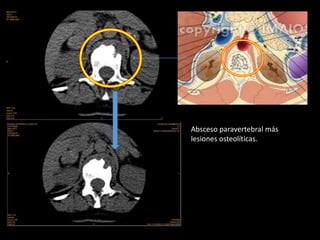

12-06-14: TEM de columna dorsolumbar:

grandes áreas de esclerosis en cuerpo

vertebral de D12 y L1, con presencia de

lesión lítica de 15x9 mm a nivel de L1.

Incidentalmente aumento de tamaño de

glándulas suprarrenales bilaterales, con

gruesas calcificaciones en glándula suprarrenal

izquierda

IMAGEN TOMOGRAFICO

Absceso paravertebral más

lesiones osteolíticas.